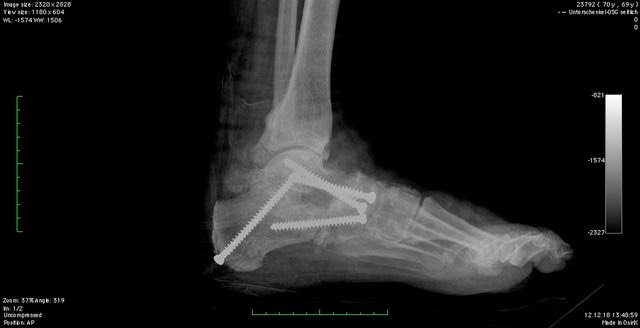

Nachbehandlung und Heilungsdauer

Die Nachbehandlung orientiert sich an der Art des Eingriffs; sie ist essenziell für ein optimales Langzeitergebnis. In der Regel erfolgt eine Ruhigstellung im Gips oder Walker in den ersten 6-8 Wochen nach der Operation mit 20 kg Teilbelastung.

Die weitere Nachbehandlung umfasst:

- Physiotherapie zur Wiederherstellung von Beweglichkeit, Kraft und Koordination

- Regelmäßige Verlaufskontrollen mit Röntgen

- Individuelle Belastungssteigerung, je nach Heilungsverlauf

- Rückkehr zu sportlicher Aktivität frühestens nach 3 bis 4 Monaten

Wie sind die langfristigen Erfolgsaussichten?

Die Praxiserfahrung von Dr. med. Gottlieb, sowie zahlreiche Studien zeigen auf, dass eine normale, auch sportliche Belastbarkeit, ohne orthopädische Hilfsmittel in den meisten Fällen erreicht werden kann. Die Voraussetzung ist eine korrekt durchgeführte Plattfußoperation!

Die Schmerzen lassen spürbar nach, das Gangbild stabilisiert sich, die Belastbarkeit im Alltag nimmt zu und die Auswahl des Schuhwerkes, welches getragen werden kann, nimmt zu.

Insbesondere wenn die Operation frühzeitig – also vor dem Eintritt fortgeschrittener Arthrose, durchgeführt wird, ist die Prognose langfristig sehr gut.